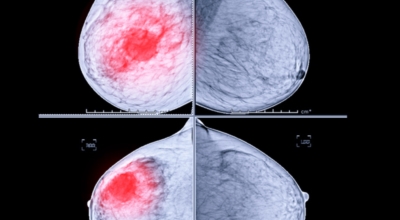

2. 유방암 초기증상 - 유방의 혹

보통 응어리가 잡히는 분들의 40%는 물혹으로 가벼운 질병으로 바로 치유가 되는 경우가 많은데요 20~30%의 확률로 유방암 초기증상일 가능성이 있다고 하죠. 따라서 매일같이 자신의 가슴을 마사지 해주시다 어느 날 응어리가 잡히게 된다면 유방암 검사 초기에 받아 보시기를 권해 드립니다.